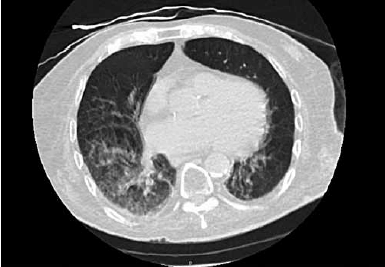

Paciente de 90 anos e admitido no pronto-socorro com história de 1 dia de evolução de tosse, sonolência e diminuição da ingestão de alimentos. Foi realizada uma tomografia computadorizada de tórax, apresentada a seguir:

(Arquivo pessoal; imagem usada com autorização)

Em relação ao caso, assinale a alternativa correta.